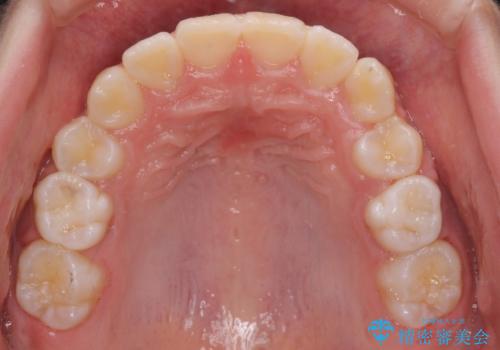

左上の犬歯が低位に埋伏しており、将来八重歯になるリスクが高いと判断されたため、補助装置とワイヤーを用いて犬歯を通常の位置まで移動させることとしました。

今後残っている乳歯が抜け、永久歯が萌出してくるため、調整可能なリンガルアーチを用いて保定を行っています。

12歳臼歯が萌出するまで経過観察を行い、すべての歯が萌出した後に、全顎矯正治療(Ⅱ期治療)を行っていきます。